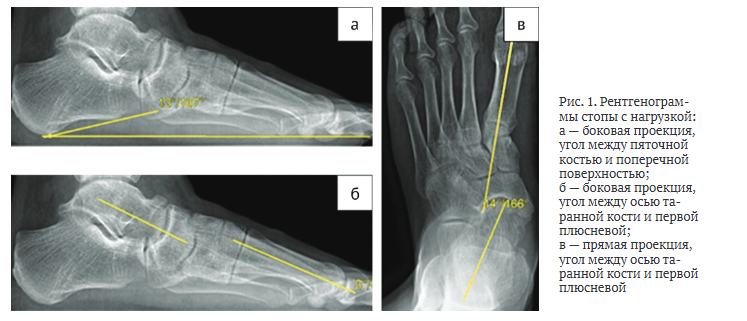

Каждому пациенту, участвующему в исследовании, при госпитализации и через год после операции проводили рентгенологическое исследование стопы с нагрузкой в двух проекциях (прямой и боковой).

На рентгенологических снимках в боковой проекции оценивали пяточно-подошвенный угол между пяточным бугром (рис. 1, а) и поперечной плоскостью, таранно-первоплюсневый угол между осью таранной кости и осью первой плюсневой кости (рис. 1, б). На прямой проекции измеряли угол между осью таранной и первой плюсневой костями (рис. 1, в). На основании измерений, проведенных до операции, оценивали степень снижения продольного свода, отведения переднего отдела стопы и вальгусную деформацию стопы, а также корригирующую способность предлагаемого метода. На следующий день после операции рентгенографическое исследование проводили без нагрузки на стопу, оценивали уровень остеотомии, положение трансплантата и металлофиксатора. Через год после хирургического лечения на контрольных рентгенограммах с нагрузкой на стопу измеряли степень коррекции деформации и ее сохранение в течение года, анализировали консолидацию области остеотомии, положение трансплантата и металлофиксатора, деформирующий остеоартроз окружающих суставов.

По результатам рентгенографии голеностопного сустава до операции получены следующие параметры: пяточно-подошвенный угол — 13°, таранно-первоплюсневый угол в прямой проекции — 14°, в боковой проекции — 3° (рис. 1). МСКТ-исследование до хирургического вмешательства не проводили. На следующий день после операции выполнили МСКТ стопы, которая выявила наличие объединённой передней и средней суставных фасет подтаранного сустава, повреждённых в ходе оперативного вмешательства (рис. 4).